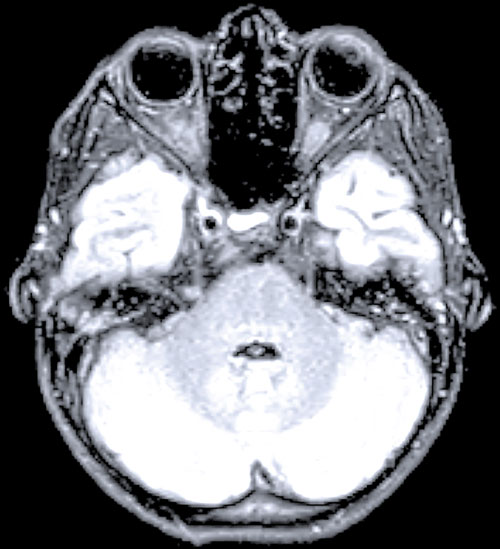

Fall 1. En 9 år gammal flicka sökte på barnakuten efter att ha haft feber i några dagar och vaknat med uttalad svaghet i höger arm. Akut DT-undersökning av hjärna visade normala fynd. Kompletterande MR-undersökning visade signalförändringar i bakre delen av pons och långsträckta signalförändringar i ryggmärgens gråa substans (mer expansiva i halsryggmärgen än i övriga ryggmärgen). Inget patologiskt kontrastmedels­upptag påvisades (Figur 1). MR ingav först misstanke om spinal tumör, men eftergranskning visade en mer tydlig inflammatorisk bild och tumörmisstanken kunde avskrivas. Lumbalpunktion visade lätt pleocytos. Mikrobiologisk utredning i blod och likvor utföll negativ. Prov från feces och nasofarynx togs inte.

Figur 1 (fall 1). Vid initial MR-undersökning visade T2-viktad sekvens expansiva signalförändringar över hela cervikala ryggmärgen (första bilden) jämfört med mer kaudala delar; axialt T2-viktad sekvens i höjd med C4 visade mer expansiv grå substans (andra bilden). T2-viktad FLAIR (fluid attenuated inversion recovery) visade förhöjd signal i bakre delen av pons (tredje bilden). Vid MR-undersökning 10 dagar senare kunde T2-viktad sekvens inte påvisa signalförändringarna i ryggmärgen (fjärde och femte bilden). På T2-viktad FLAIR har signalförändringarna i pons gått i regress (sista bilden).